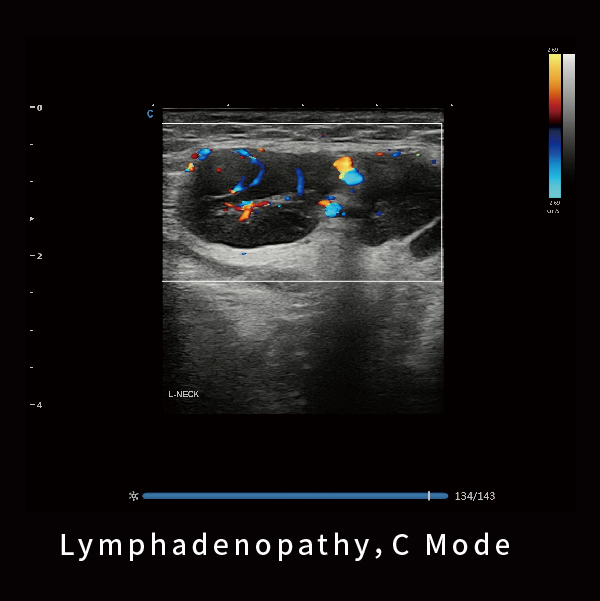

淋巴结,C模式